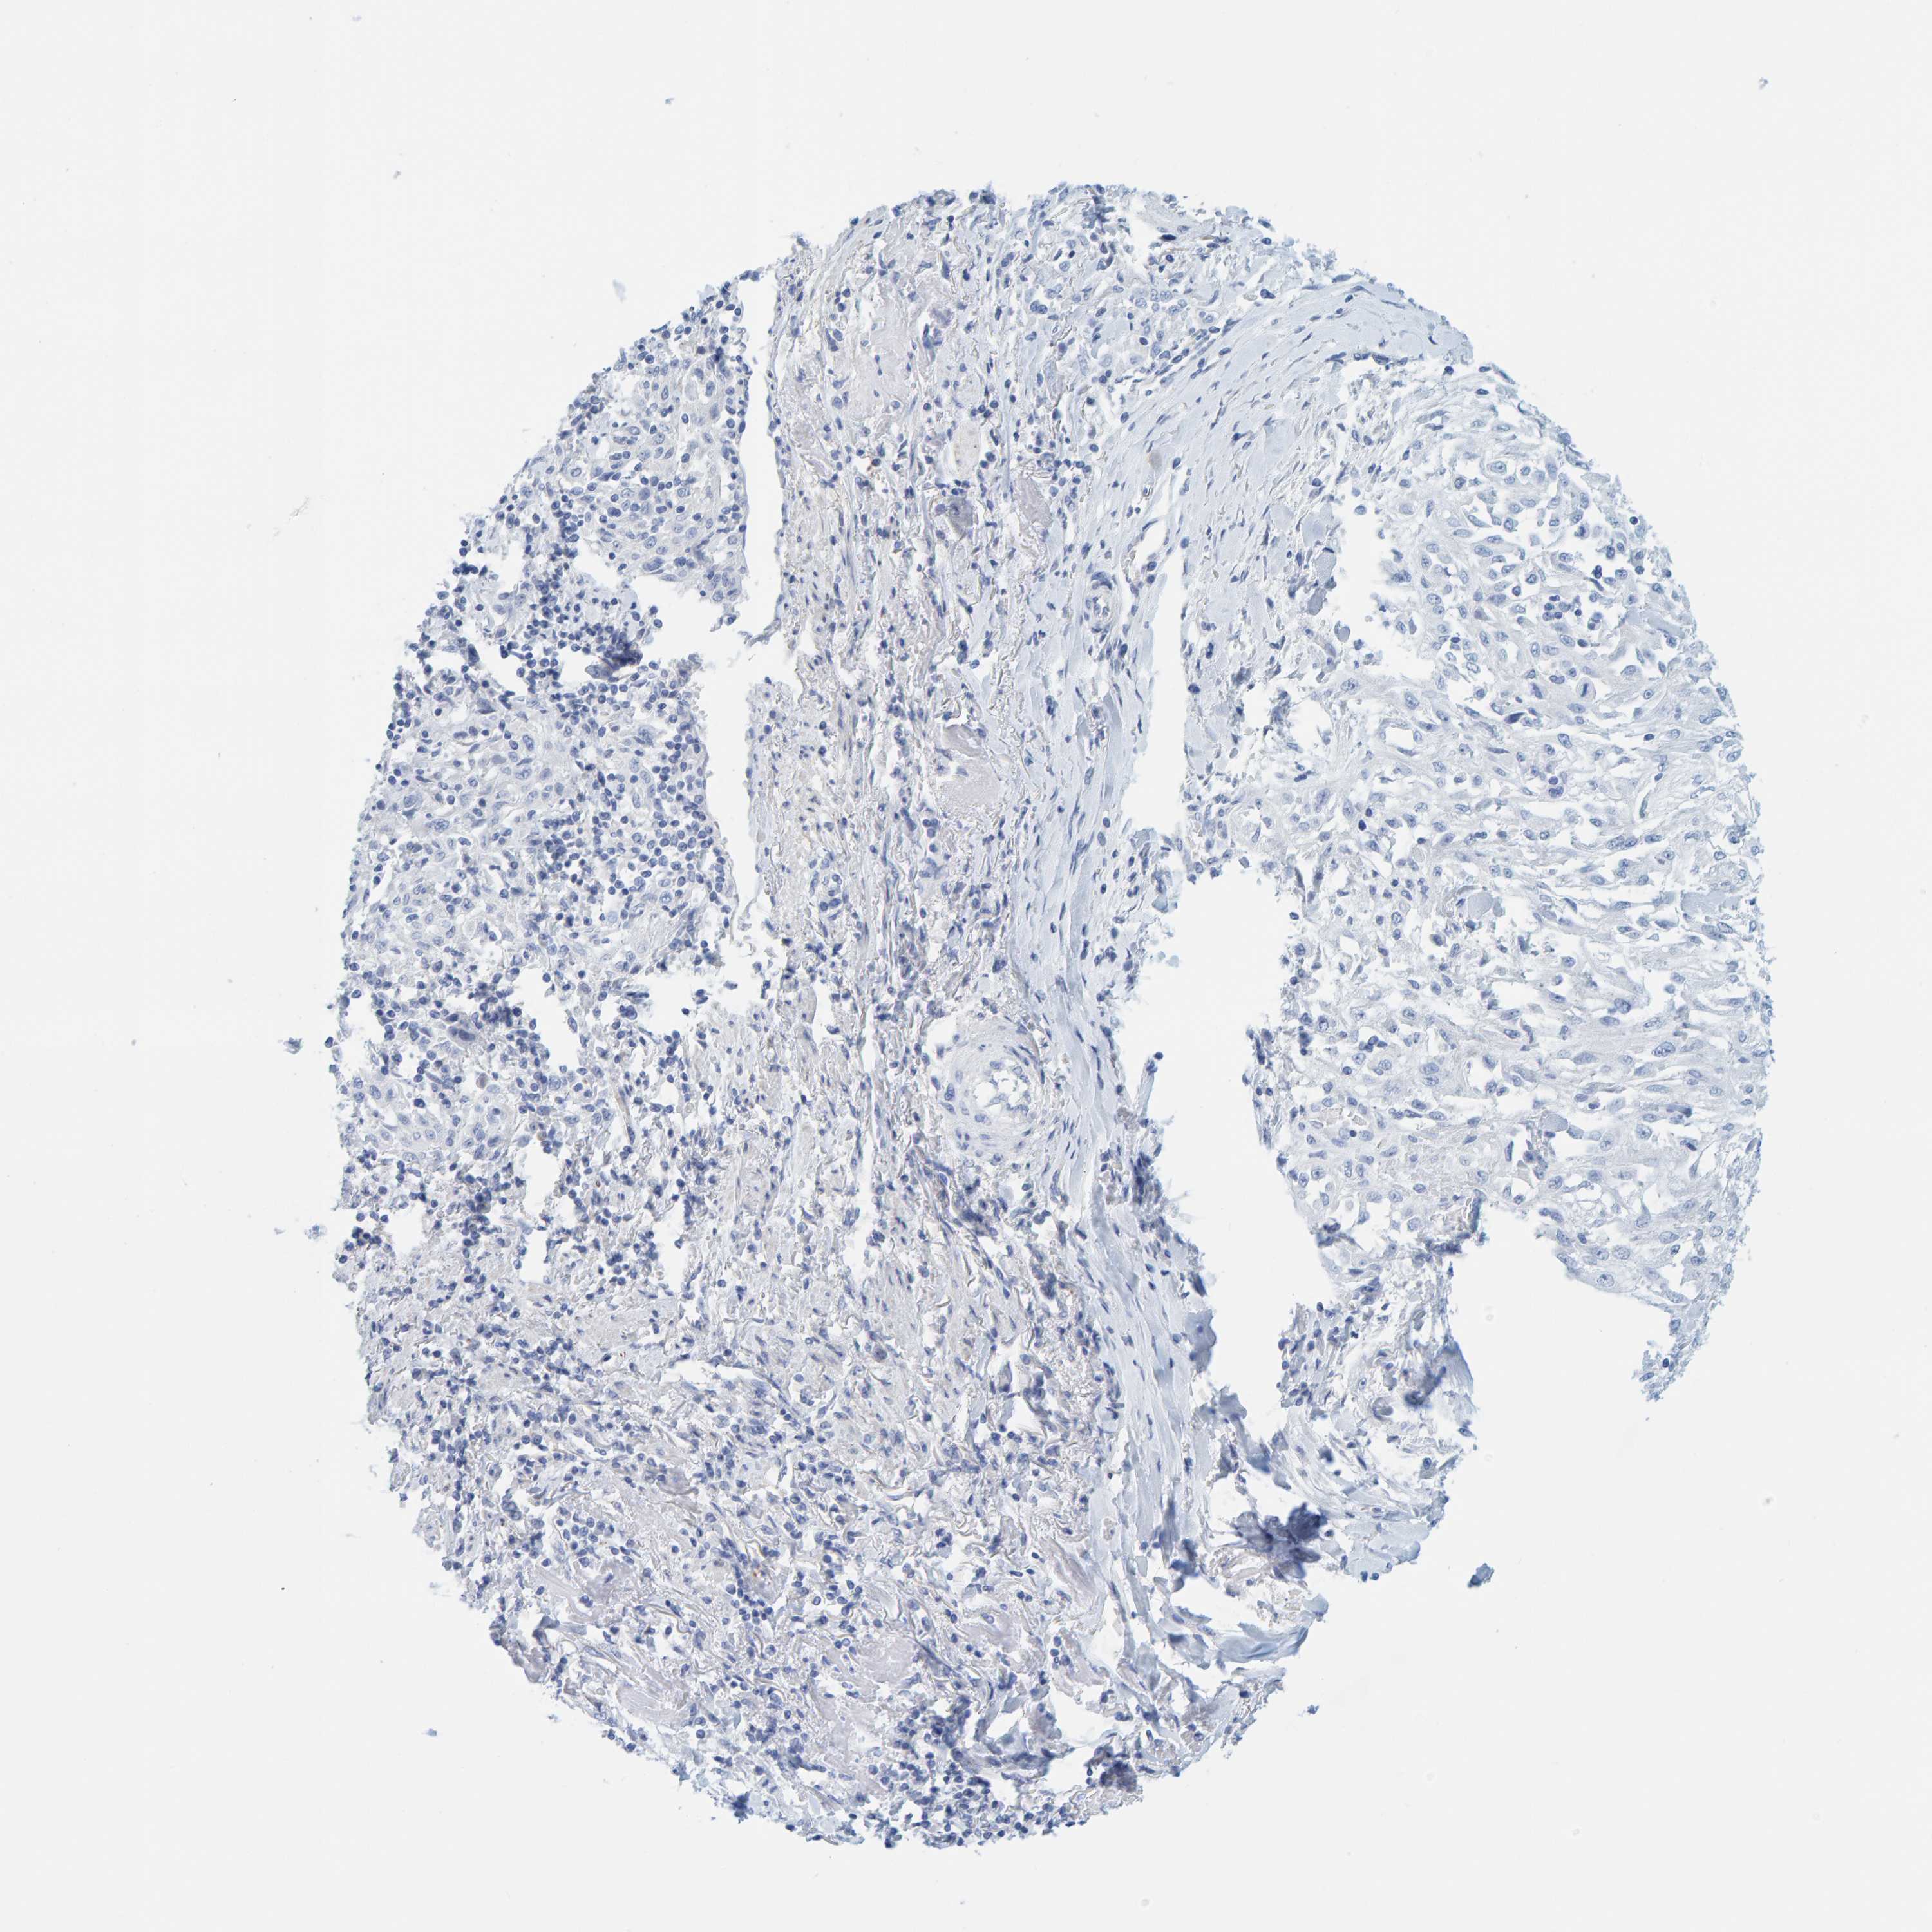

SKIN CANCER - Protein expressioni

A mouse-over function shows sample information and annotation data. Click on an image to view it in a full screen mode. Samples can be filtered based on level of antibody staining by selecting one or several of the following categories: high, medium, low and not detected. The assay and annotation is described here.

Antibody staining in the annotated cell types in the current human tissue is reported as not detected, low, medium, or high, based on conventional immunohistochemistry profiling in selected tissues. This score is based on the combination of the staining intensity and fraction of stained cells.

Each image is clickable and will lead to virtual microscopy that enables deeper exploration of all samples and also displays staining intensity scores, fraction scores and subcellular localization as well as patient and tissue information for each sample.

Antibody HPA023021

Basal cell carcinoma